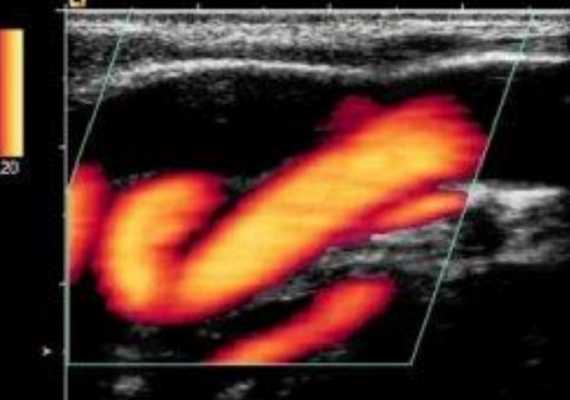

УЗДГ при аномалиях строения сонных артерий

Дуплексное сканирование занимает лидирующее место в диагностике врожденных и приобретенных пороков магистральных сосудов шеи. Метод позволяет не только выявить дефект, но и охарактеризовать особенности кровотока в зоне интереса. Наибольшую угрозу представляет патологическая извитость внутренней сонной артерии с выраженными локальными нарушениями гемодинамики, поскольку такое состояние может стать причиной инсульта и транзиторной ишемической атаки.

Деформации ВСА указанного типа по распространенности уступают только их атеросклеротическому поражению и часто сочетаются с артериальной гипертензией и атеросклерозом.

Патологическая извитость ВСА на УЗ-изображении